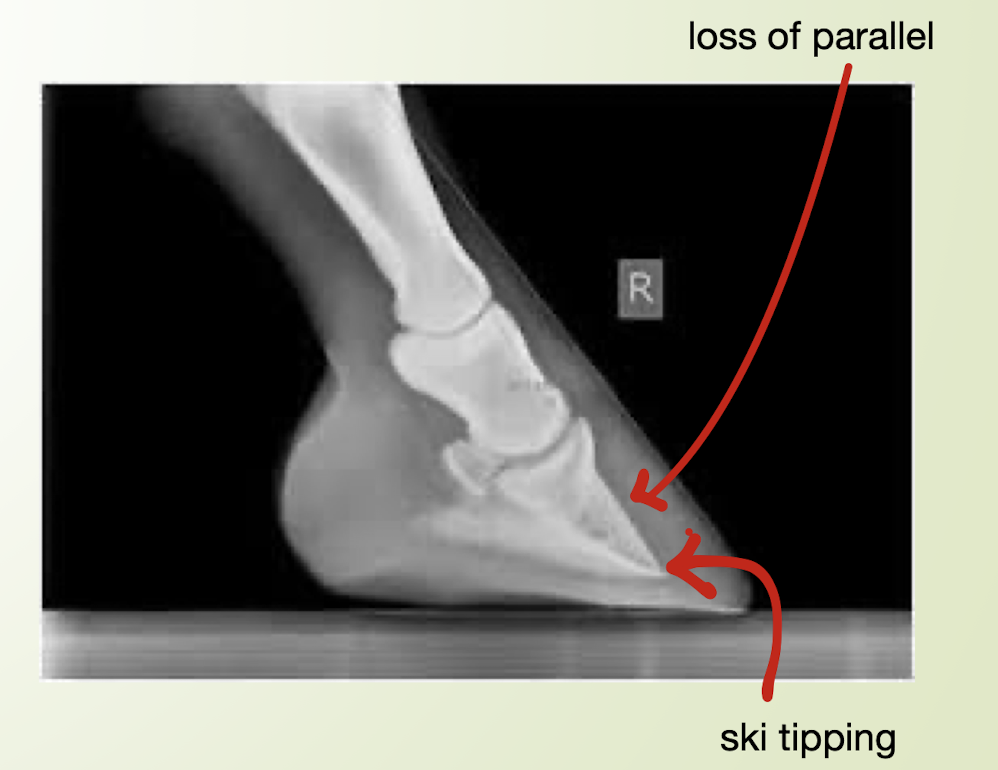

what are the abnormal signs seen in an chronic laminitis radiograph?

A

ski tipping of P3

loss of parallel between dorsal hoof wall and dorsal P3

medial to lateral asymmetry

sinking